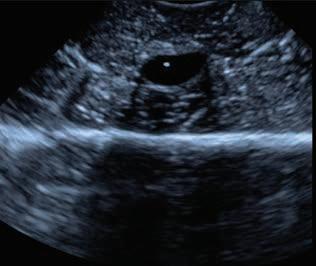

A 3-year-old, male neutered Labrador Retriever presented for chronic diarrhoea. t he patient had a history of inflammatory bowel disease and had undergone multiple previous surgeries for foreign body removal. A colopexy had also been previously performed. t he patient had completed a course of metronidazole on the day of presentation and was also receiving vitamin B12, psyllium husk (metamucil) and probiotics. He was up to date with de-worming treatment and core vaccinations. A three-view abdominal radiograph series was taken as part of the diagnostic workup, and two cropped projections are provided below (Figure 1).

Figure 1. l eft lateral (a) and ventrodorsal (b) abdonimal radiographics of a dog with chronic diarrhoea.

a b